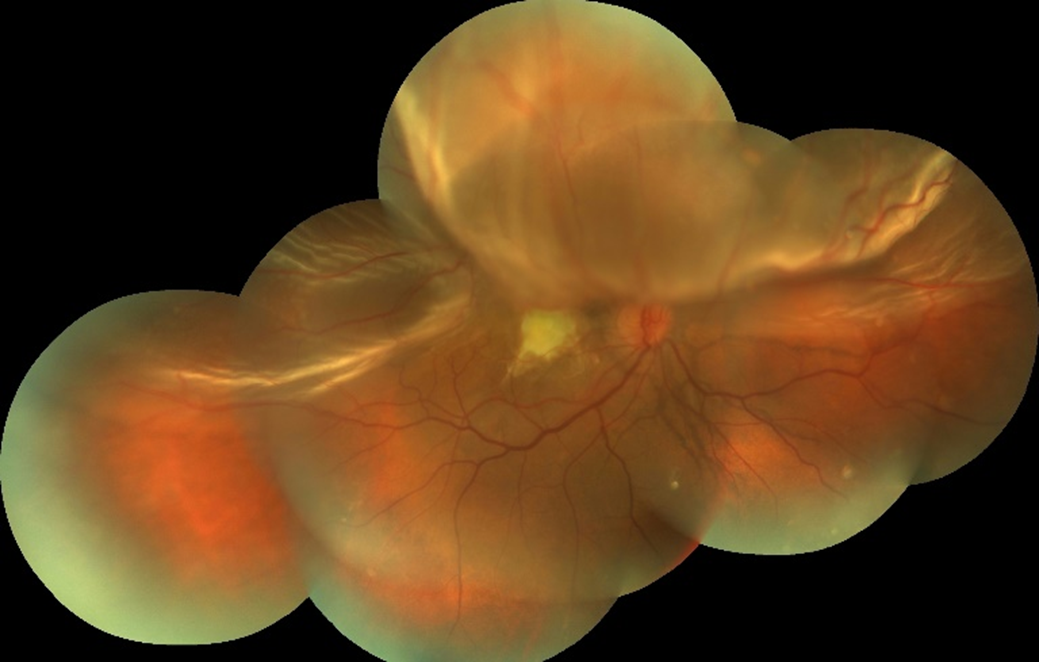

Sağ gözde beş gündür artan görme azlığı olan 30 yaşındaki kadın hastanın renkli ...